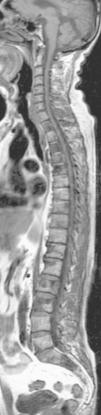

La RM mielografía se trata de una técnica no invasiva, que proporciona información anatómica del espacio subaracnoideo. La ventaja en relación con otras técnicas radiológicas incluye la ausencia de radiación ionizante, el carácter no invasivo y que no es necesario administrar contraste por vía intratecal. La técnica proporciona una visualización de todo el saco tecal (fig. 2), incluso si hay estenosis, bloqueo o adherencias que hubieran condicionado un bloqueo del contraste en la mielografía radiográfica. La ventaja de la técnica es su aplicación conjuntamente con las secuencias clásicas de cualquier estudio de RM, sin necesidad de estudios suplementarios y que puede realizarse en un único examen de RM. Las posibles indicaciones para utilizar esta secuencia suplementaria son en valoraciones de variantes anatómicas radiculares, anomalías congénitas, pseudomeningoceles postraumáticos, aracnoiditis adhesiva, tumores, hernias discales, estenosis de canal degenerativa o malformaciones arteriovenosas5.